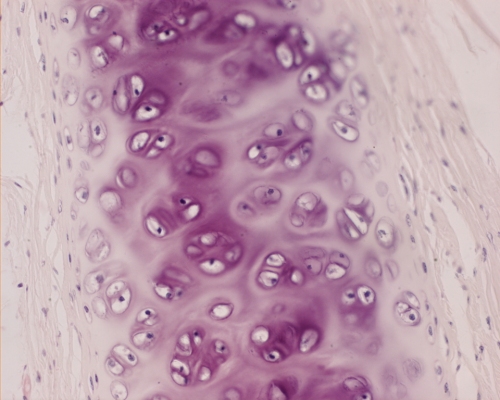

Type II collagen, a fibrillar collagen of cartilage, is composed of three identical alfa-chains called alfa-1(II).

• Cartilage consists primarily of fibrils of type II collagen in the form of arcades that are distended by highly charged GAGs.